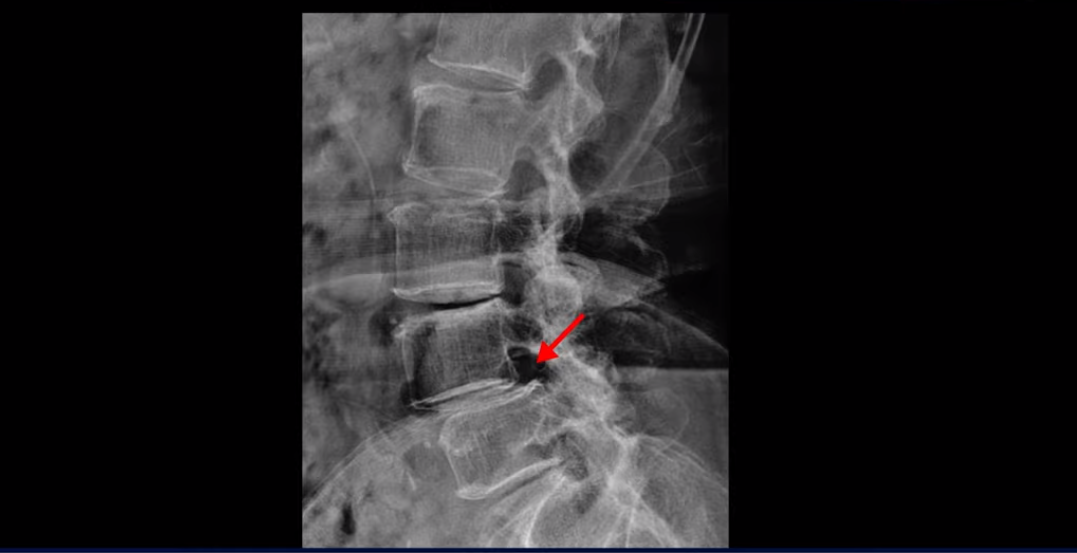

X-ray로 보면 뼈가 밀려 나간 게 더 잘 보입니다.

4번 5번에는 뼈가 밀려 나간 전방전위증도 있습니다.